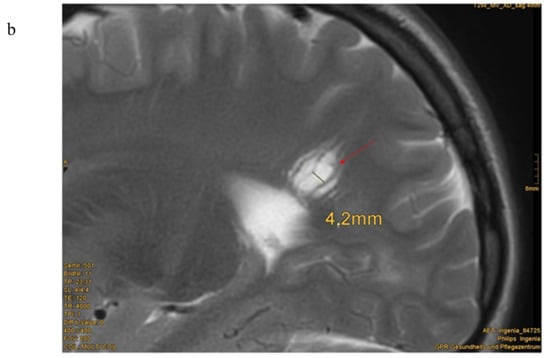

Eighteen of nineteen patients exhibited variations in cMRI. In 17 of 19 patients, we were able to re-analyze the MRI scans. In two cases, we only obtained medical reports, which were reported to be normal, even though enlarged perivascular spaces were described in one of these two patients. Medical reports of our patient cohort described enlarged perivascular spaces (EPVS), also known as Virchow–Robin Spaces (VRS), in six patients. However, when we re-analyzed the MRI pictures with special focus on EPVS, we found enlarged perivascular spaces in a total of eighteen patients (18/19). In some patients, these findings were quite evident (Figure 1b). Seven patients (7/17) presented with white matter abnormalities (Figure 2). Further pathologies included a cavernoma at the right side of the cerebellum, subependymal heterotopia at the top of the lateral cerebral ventricle, arachnoid cysts (in two), a Chiari malformation type I and a clinical diagnosis of pseudotumor cerebri with ventriculoperitoneal shunt in one patient (Table 1).

Figure 1.

Enlarged perivascular spaces (EPVS) in cerebral MRI (a) Patient 15: 4.5 year-old boy, T2w-image, EPVS 2 mm diameter [Courtesy Kinderkrankenhaus Kliniken der Stadt Köln]. (b) Patient 23: 12.5 year old girl, T2 weighted image, sagittal view, pronounced EPVS up to 3 mm diameter [Courtesy Dr. A. Wieschen, Institut für Radiologie und Nuklearmedizin, GPR Klinikum Rüsselsheim].